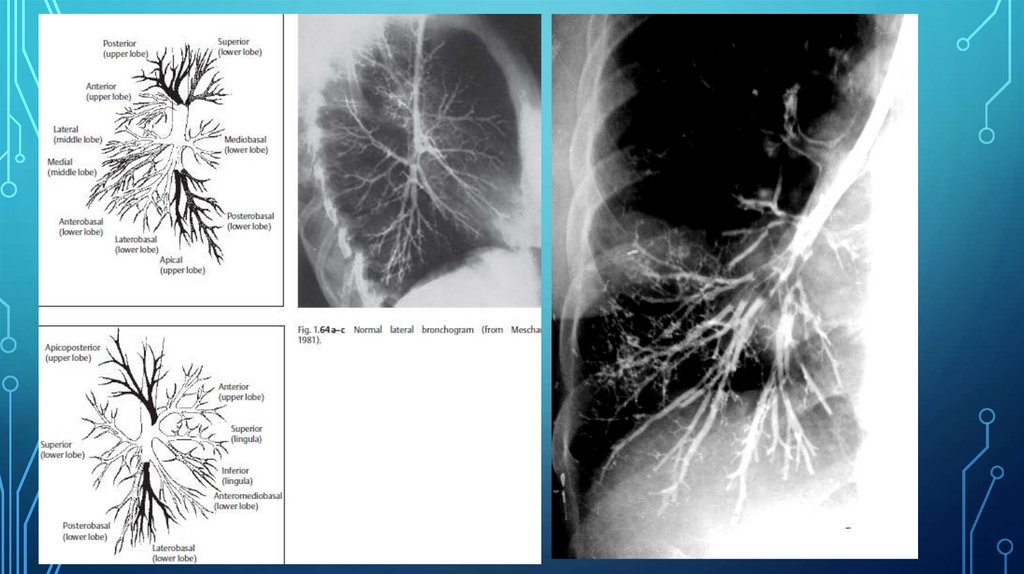

Долевое и сегментарное строение легких (Лондонская классификация 1949г)

Рис. 17а. Диагноз: Абсцедирующая пневмония правого легкого.

Рис.8а. Диагноз: Гангрена нижней доли правого легкого.

Рис. 11. Диагноз: Фиброзно-кавернозный туберкулез. Слева определяется гигантская полость распада.

29.39M

Category: medicinemedicine

Рентгенодиагностика_заболеваний_органов_грудной_клетки_презентация

1. Рентгенодиагностика заболеваний органов грудной клетки

РЕНТГЕНОДИАГНОСТИКА ЗАБОЛЕВАНИЙ

ОРГАНОВ ГРУДНОЙ КЛЕТКИ

Ассистент кафедры онкологии с курсом лучевой

диагностики и лучевой терапии

Малов Алексей Анатольевич

23. Долевое и сегментарное строение легких (Лондонская классификация 1949г)

ДОЛЕВОЕ И СЕГМЕНТАРНОЕ СТРОЕНИЕ

ЛЕГКИХ (ЛОНДОНСКАЯ КЛАССИФИКАЦИЯ 1949Г)

Правое легкое

верхняя доля

1-верхушечный

2-задний

3-передний

средняя доля

4-латеральный

5-медиальный

нижняя доля

6-верхушечный

7-медиальный базальный

8-передний базальный

9-латеральный базальный

10-задний базальный

24. Долевое и сегментарное строение легких (Лондонская классификация 1949г)

Левое легкое

1+2 –верхушечно-задний,

4-верхний язычковый

5-нижний язычковый